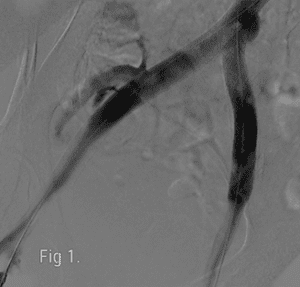

Authors: Tae An Choi ANP-BC, Hiral Patel PA-BC, Nay Htyte MD FACC and Back Kim MD FACC. Heart Vein NYC, New York, NY (Figure 1, left) Venous read more